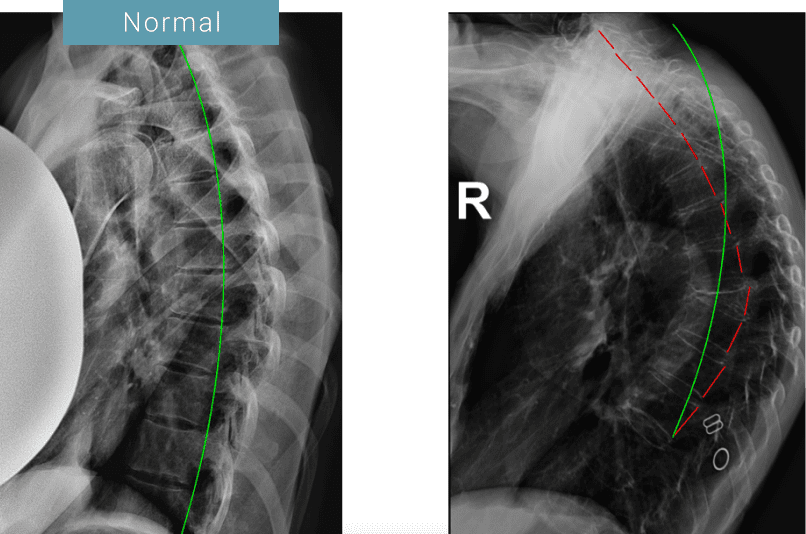

Your Partner in Managing Scoliosis and Hyperkyphosis

At 100+Living, we understand that scoliosis and hyperkyphosis are more common than many people realize. Unfortunately, these spinal conditions are often mismanaged. As one of only two Advanced Certified Chiropractic Biophysics (CBP) offices in all of Western Canada, we are uniquely equipped to provide the highest level of care for these conditions. We also work with one of the most qualified and experienced ScoliBrace providers in the world, Dr. Brad Gage, to support for cases that qualify, ensuring comprehensive and personalized treatment options.